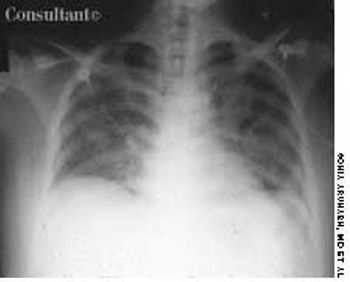

A 30-year-old man, who was homeless, was admitted to the hospital with a several-month history of dyspnea and fever. He complained of producing excessive sputum and having frequent bouts of hemoptysis. Bilateral crackles were heard during examination of the lungs. The patient was in acute respiratory distress and was intubated to provide ventilatory support.